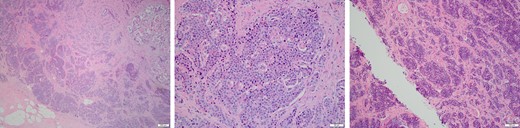

At this most recent visit, physical exam was unremarkable. The patient denied new symptoms including palpable masses, pain, nipple discharge/retraction, skin change, or lymphadenopathy. Diagnostic mammogram was concerning for a suspicious left breast mass (0.6 × 0.5 × 0.5 cm) at the 6:30 position located 4 cm from the nipple and categorized as BI-RADS 4 (Fig. 1). The mass was biopsied, and tissues sent to pathology for diagnosis. The morphology was consistent with the patient’s previous carcinoid tumor (Fig. 2), and tissues stained positive for CD56, CDX2, Chromogranin, and Synaptophysin (Fig. 3). Additionally, tissues were negative for CD117, Estrogen/Progesterone receptors (ER/PR), GCDFP, HER2-Neu, p63, and TTF-1. The tumor had a low proliferative index, with >2 mitoses per high power field. These findings supported a diagnosis of a metastatic, well-differentiated, Grade 2/3 neuroendocrine tumor.

Tissues were stained for CD56, Chromogranin, and Synaptophysin expression, affirming a diagnosis of a metastatic ileal carcinoid tumor.